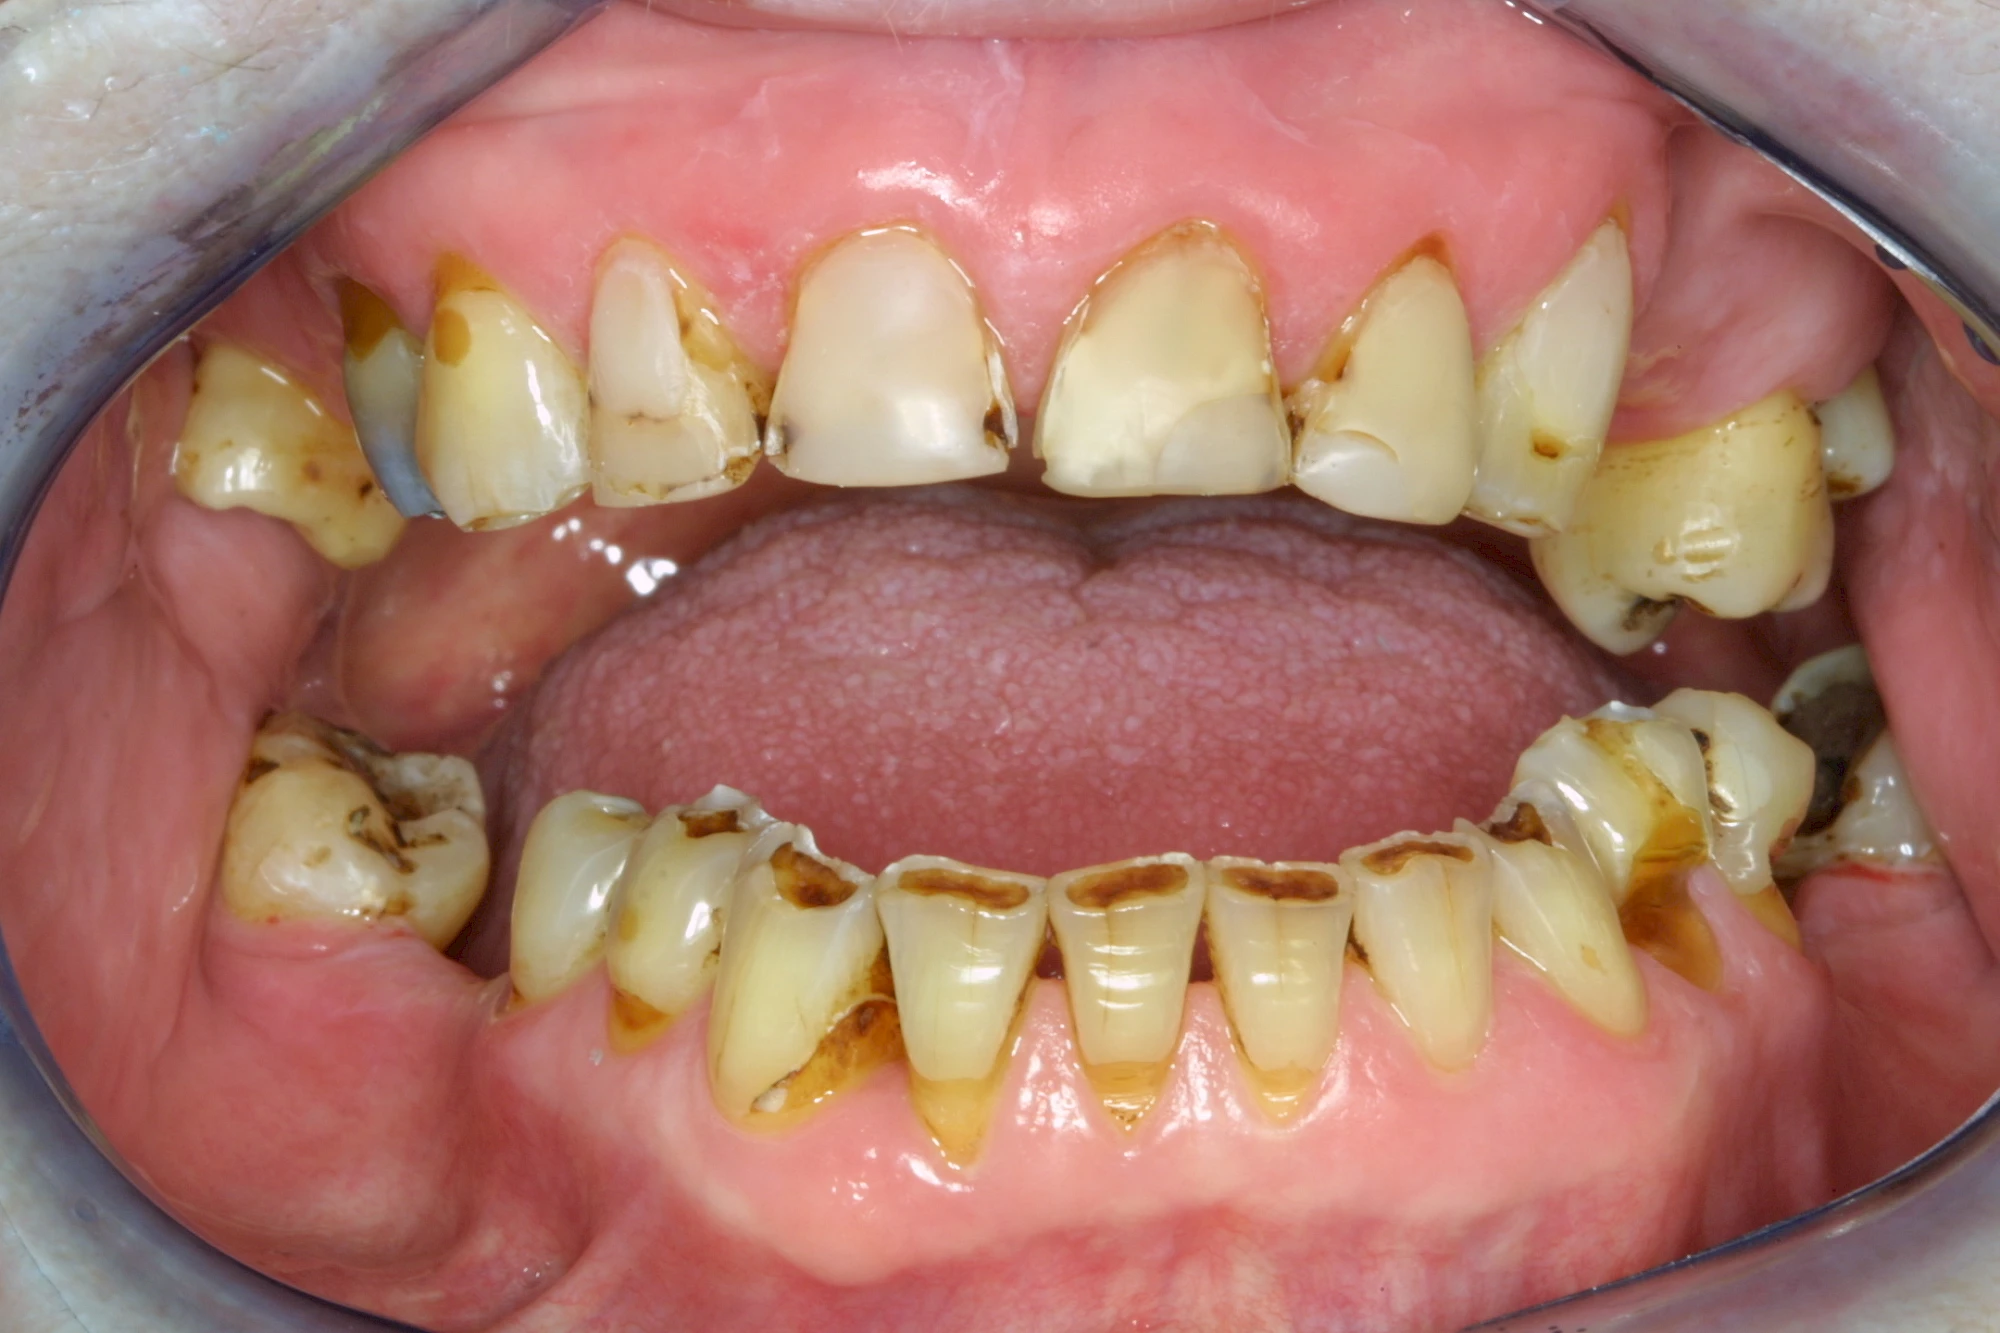

Auswaschung (Erosion) dagegen ist eine Verschleißerscheinung der Zähne aufgrund von immer wiederkehrenden Säureangriffen durch die Nahrung, verstärkt zum Beispiel durch den Genuss säurehaltiger Getränke oder Speisen. Auch bei Menschen mit einer Essstörung (z. B. Bulimie) können die Zähne durch die Magensäure ausgewaschen erscheinen.